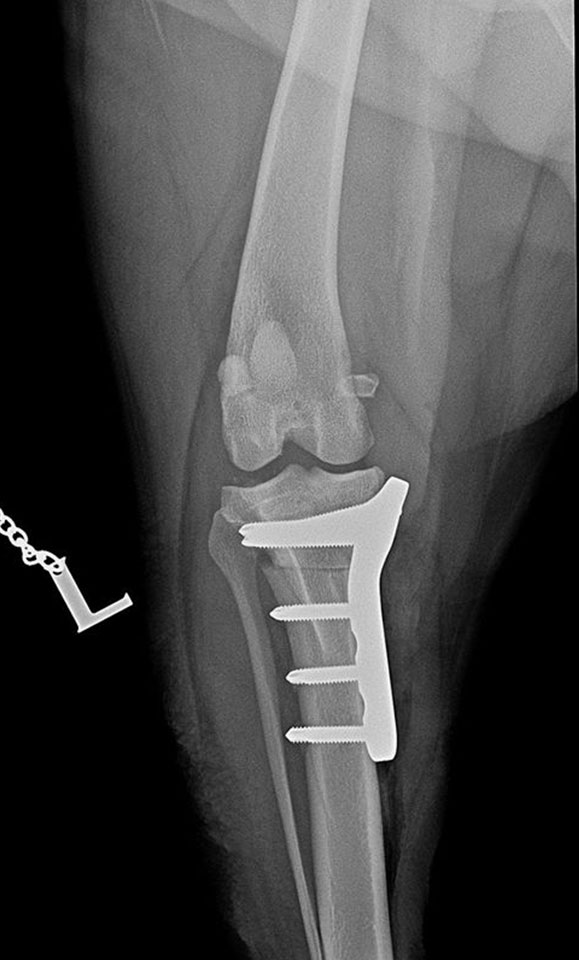

Shar-pei, cruciate ligament rupture surgery

16 June 2021